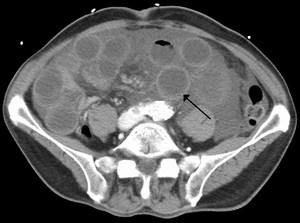

| Computer tomography (CT) showing dilated loops of small bowel with thickened walls (black arrow), findings characteristic of ischemic bowel due to thrombosis of the superior mesenteric vein. | |

Findings on CT scan include:

- Mesenteric edema[22]

- Bowel dilatation[22]

- Bowel wall thickening[22]

- Intramural gas[22]

- Mesenteric stranding[25]